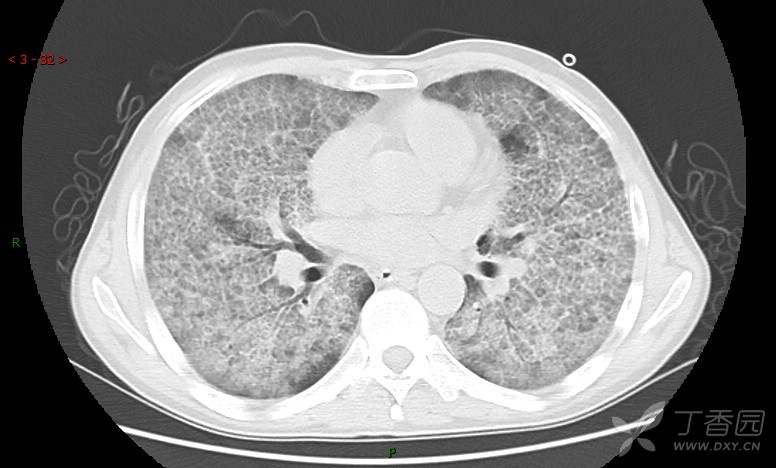

地图+铺路石征=PAP?那升高的CEA怎么说(病例3连发,附其他2例链接)

患者男,42岁,咳嗽半年余,加重伴憋喘2月余。

肺内弥漫性网状结节影,PET-CT却无阳性病灶,这是?(附其他2例链接)